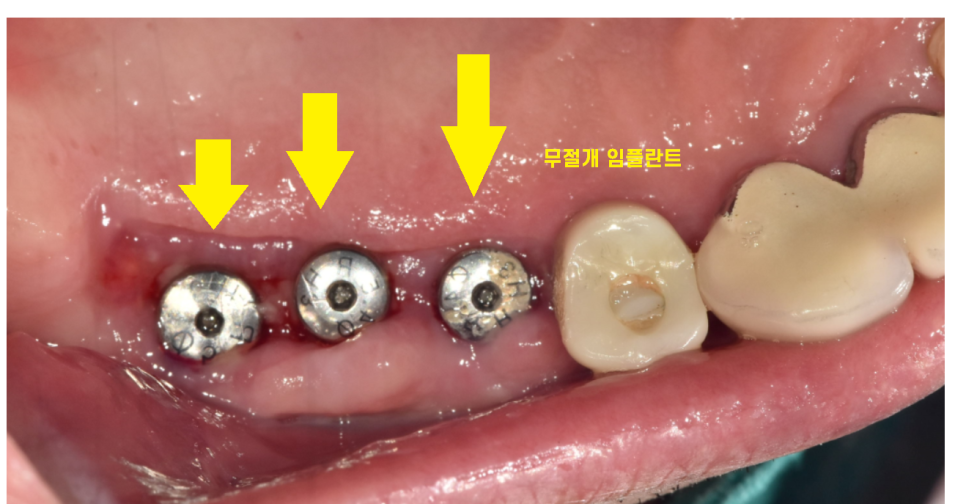

천호동 치과에서는 90% 이상의 수술을

무절개로 시행합니다.

잇몸에 작은 구멍을 내어

천호동 임플란트를 식립하는 것인데요.

수술 시간이 짧다

감염 , 출혈, 통증이 적다

환자분들께 좋기 때문에

천호동 임플란트 무절개 방식으로 적극 진행합니다.